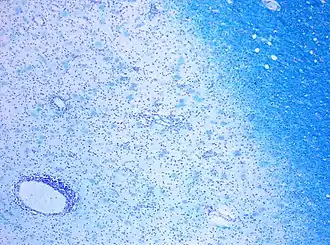

![]() | |

| CD68-stained tissue shows several macrophages in the area of a demyelinated lesion caused by MS. | |